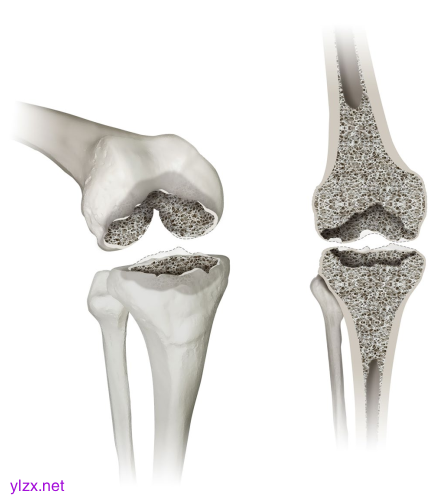

显示膝关节缺陷分类(KDC)的1型缺陷。1型的特征是股骨和胫骨骨骺骨的孤立缺陷。左图为3D斜视图,右图为正视图